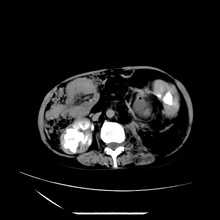

女性,41岁,发现左腹部包块3年,现行ct检查,检查前做过静脉肾盂造影。

左侧低密度区是脂肪密度,中间可见条索状软组织样密度影,现主要想知道左肾前下缘圆形软组织样密度影,内见低密度水样密度影,这是什么?

脾脏增大,左肾后方脂肪增多,脊柱前方脂肪增多,左肾窦脂肪增多,左肾变形,双肾积水以左侧为著,左肾内侧及上方见环形软组织肿物影,内部低密度区,考虑1盆腹腔/腹膜后及左肾窦脂肪增多症2左肾内侧病灶可能为左肾上腺病灶,可能为脂肪增多的原凶

1)考虑左肾替代性脂肪瘤病;不排除左肾错构瘤。2)双肾积水。

诊断rsl的必备条件是肾窦、肾门的脂肪组织增生和肾实质的萎缩,而且本例因为ivp后扫描不好判断有无肾结石但可能性较小;另外,占位效应显著,脾后缘都受压了,肾门以下肾实质残缺,支持肾脏错构瘤.

腹膜后脂肪肉瘤累及左输尿管及左肾窦脂肪沉积,双肾积水,